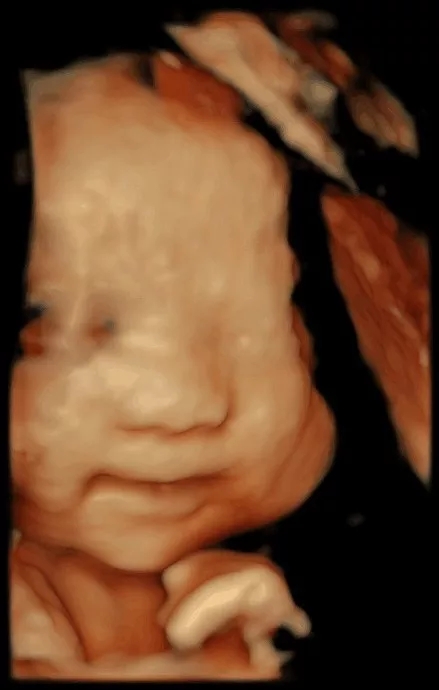

也许肚子里的宝宝

还不能说TA们对妈妈的爱

但通过美琳达的四维彩超画面中

TA们的活泼好动,萌萌的表情

已经说明了一切